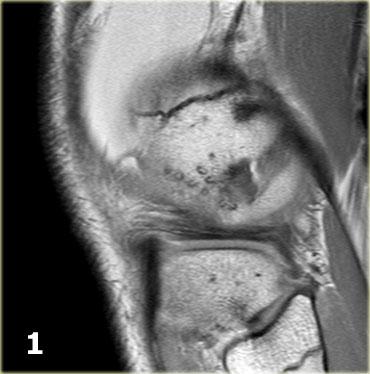

Gãy xương Segond và rách sụn chêm

Gãy xương Segond là tổn thương bong gân (avulsion) của dây chằng bao khớp bên ngoài.

Cơ chế chấn thương là xoay trong kết hợp với lực varus.

Trên phim X-quang, tổn thương biểu hiện dưới dạng một mảnh xương hình bầu dục tách rời khỏi mặt ngoài đầu gần xương chày (hình).

Gãy xương Segond có mối liên quan chặt chẽ với rách dây chằng chéo trước (75-100%) và tổn thương sụn chêm trong và ngoài (66-70%).

Trên phim X-quang, gãy xương Segond có thể dễ bị bỏ sót (mũi tên đỏ).

Lưu ý rằng còn có thêm tổn thương bong gân của dây chằng bên trong.

Tiếp tục xem các hình ảnh MRI.

Bên trái là ba lát cắt coronal PD liên tiếp:

-

Rách bó dây chằng bên trong sâu (mũi tên vàng).

Bong mảnh xương ở mặt ngoài đầu gần xương chày, tức là gãy xương Segond (mũi tên đỏ). -

Lưu ý mảnh sụn chêm phía trong bị di lệch.

Điều này cho thấy còn có thêm rách dạng quai xô (bucket handle tear). -

Ngoài rách dạng quai xô (mũi tên xanh phía trong), còn có một đường rách ngang khó nhận thấy ở phần ngoại vi của sụn chêm (mũi tên xanh phía ngoài).

Đường rách ngang này được thể hiện rõ hơn trên các hình ảnh khác (không trình bày ở đây).